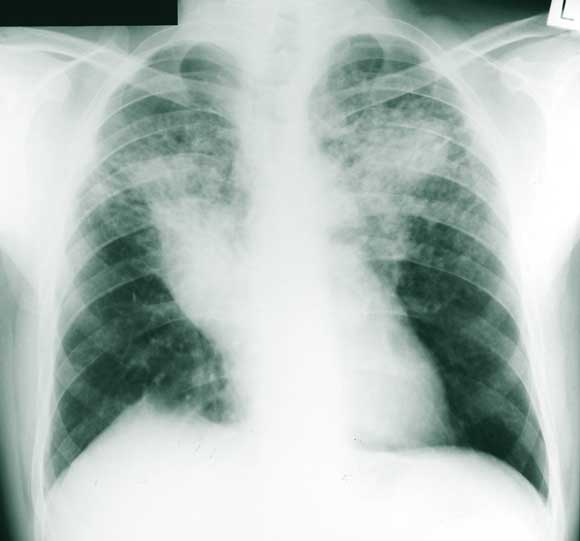

A number of measurements showed that the patient’s sarcoidosis was stable: serum angiotensin-converting enzyme and 24-hour urine calcium levels were normal; respiratory function testing showed moderate air flow obstruction and gas transfer, with no change from previous measurements; and a chest x-ray (Figure 3) showed no new changes.